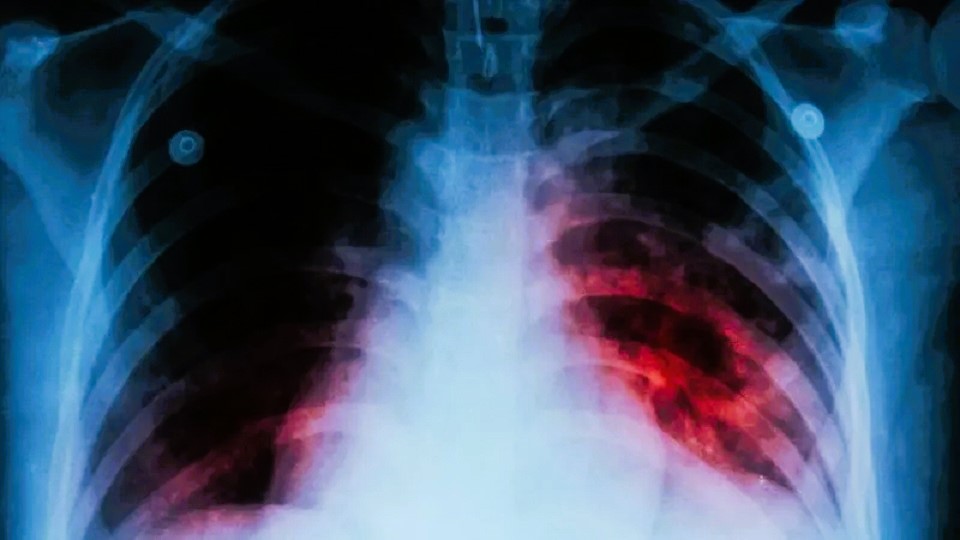

Tegucigalpa, Honduras.- La tuberculosis vuelve a posicionarse como una de las principales amenazas a la salud pública en Honduras, luego que la doctora Odalis García, jefa del Programa de Enfermedades Transmisibles del Hospital Cardiopulmonar, conocido como el Hospital del Tórax, confirmara que hasta abril de 2025 se han contabilizado 705 casos de tuberculosis a nivel nacional.